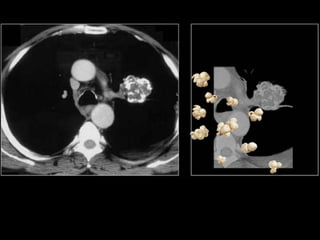

Calcification of lung nodules

o Laminated: TB Granuloma

o Central or target: Histoplasmoma

o Popcorn: Hamartoma